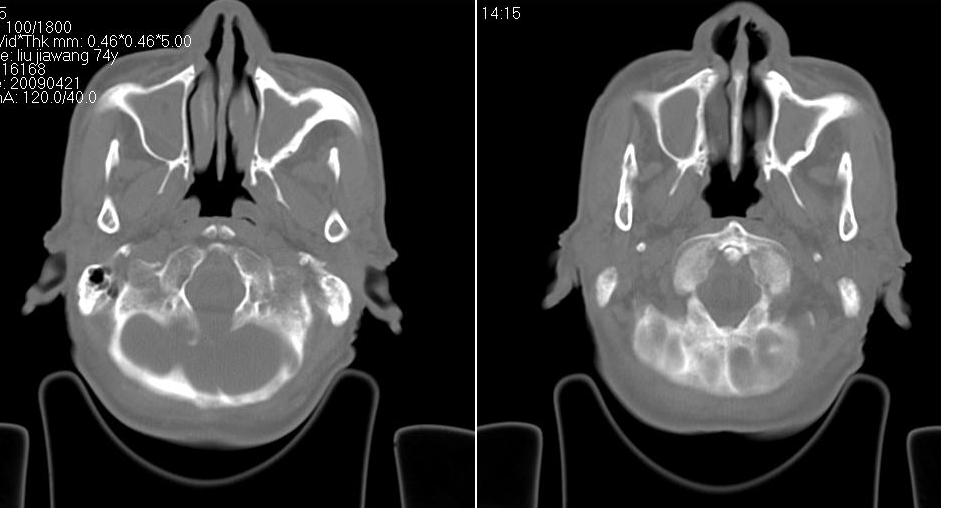

以下是引用zrs在2009-4-21 18:22:00的发言:[br]左侧额窦、筛窦及上颌窦内均充以软组织密度影,且窦壁骨质明显增厚,右侧上颌窦粘膜环形增厚。左侧鼻腔内亦见软组织密度影。考虑慢性鼻窦炎。

以下是引用hnfsh在2009-4-21 19:56:00的发言:[br]病灶主体位于左侧鼻腔内,呈膨胀性生长,鼻中隔、左侧筛板骨质吸收破坏,双侧上颌窦、额窦内聪充满软组织密度影。 考虑:1。左侧鼻息肉 2。慢支副鼻窦炎

以下是引用张xyz在2009-4-21 20:59:00的发言:[br]全组副鼻窦炎并息肉样变[br]